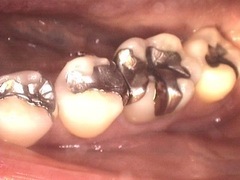

セラミックインレー

セラミックを使用した詰め物です。当院ではe-maxという新しいセラミック素材を使用しており、強度が高く天然の歯に近い透明度を持っています。

1本 55,000〜60,500円(税込)

浸潤麻酔下にてメタルインレーを除去、色調のチェックを行い、印象および咬合採得。

1週間後にセラミックインレー装着。

処置回数は2回。2本で115,500円(税込)

リスクとしては冷水痛を起こす可能性あり。